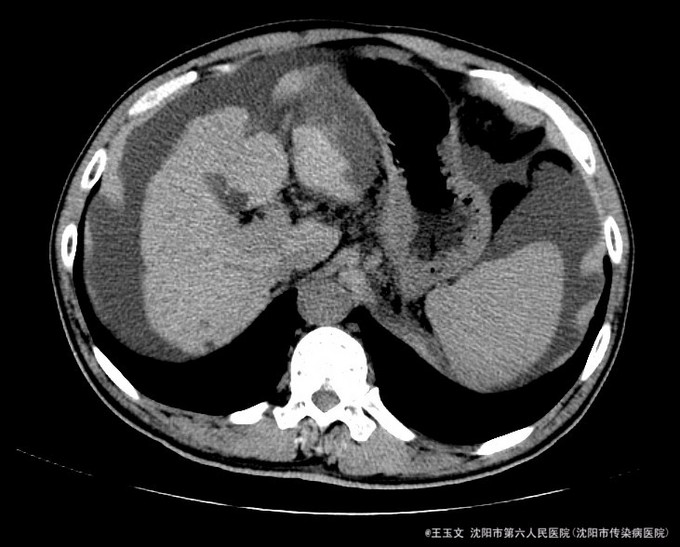

查体:神志清,巩膜无黄染,心肺听诊无异常,腹软,无压痛,肝区无叩痛,移动性浊音阳性,双下肢无浮肿,扑翼样震颤阴性。可见肝掌和腹水等阳性体征 化验结果:天门冬氨酸氨基转移酶 48 U/L、胆碱酯酶 3254 U/L、总蛋白 84.0 g/L、总胆红素 39.9 umol/L、非结合胆红素 26.7 umol/L。凝血酶原时间 15.5 秒、凝血酶原比率 1.35 、凝血酶原百分活动度 54.9 %、活化部分凝血酶原时间 40.7 秒、纤维蛋白原含量 1.255 g/L、D-二聚体 3.05 ug/ml↑。乙型肝炎病毒表面抗原 阳性(+) ↑、乙型肝炎病毒e抗体 阳性(+) ↑、乙型肝炎病毒核心抗体 阳性(+) 。甲胎蛋白(AFP) 11.52 ng/mL。 超声检查示:肝硬化,较多腹水,肝内见多个低回声,较大约1.5*1.0厘米,边界清晰。 肝增强ct:肝脏边缘欠规整,肝裂增宽,各叶大小比例失调,肝实质内见多个低密度结节,较大位于Ⅳ段,大小约2.04cm,增强扫描动脉期Ⅳ段两个结节中等强化,门脉期及延迟扫描呈低密度,余结节无明显强化;肝内亦见多个小囊性密度灶,较大约1.44cm,无强化。肝内外门静脉显示清晰,脾脏增大增厚,超过肝脏下缘,胆囊不大,壁增厚,其内密度均匀,胰腺形态密度无特殊。肝内外胆管未见明显扩张,腹膜后未见明显肿大淋巴结。食管下段胃底贲门区见扩张扭曲的血管影。肝周及腹膜间隙见有中等量液性密度影。

诊断:初步诊断:1、乙肝肝硬化 失代偿期; 确定诊断:乙肝肝硬化 活动性 失代偿期C-P B级 行肝脏增强CT后补充诊断:肝占位性位病变 行DSA下肝动脉造影后修订诊断:原发性肝癌 治疗:限盐饮食,口服利尿剂,减少水钠储留,促进腹水消退,静点异甘草酸镁保肝治疗,行增强CT检查,发现肝内占位,考虑恶性可能大,患者肝功改善后,于局麻下DSA下行肝动脉造影及TACE治疗

术后患者未见TACE治疗并发症,无不适,复查化验结果:天门冬氨酸氨基转移酶 41 U/L、胆碱酯酶 1901 U/L、白蛋白 29.3 g/L、总胆红素 24.6 umol/L。甲胎蛋白测定:甲胎蛋白(AFP) 7.75 ng/mL。患者肝功改善,术后一周时候复查CT示病灶碘油沉积尚好,办理出院。 本例患者比较典型,虽然其术前甲胎蛋白不高,但其增强CT有典型的“快进快出”特征,并且乙肝背景,有经验的医师会考虑其为原发性肝癌的可能非常大, TACE治疗即可以确诊其肝癌,又能在确诊的同时给予治疗。